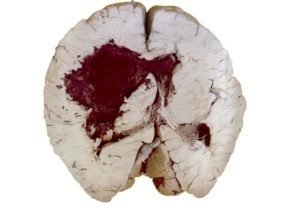

Кровоизлияние в мозг как причина разных зрачков

Травмы головы, вызванные внешним воздействием, например, падением или ударом, приводят к неравномерному диаметру зрачка. Церебральные кровоизлияния происходят внутри черепа и не вызывают внешних симптомов. Попадание большого количества крови в ткани мозга приводит к сдавливанию структур.

Если нервы (нервы мозга), отвечающие за расширение и сужение зрачков, сдавливаются с одной стороны, а кровотечение на противоположной стороне не вызывает сдавливания, зрачки становятся разного диаметра.

Опасными для жизни симптомами тяжелого кровоизлияния в мозг являются спутанность и потеря сознания, а также конвульсии.